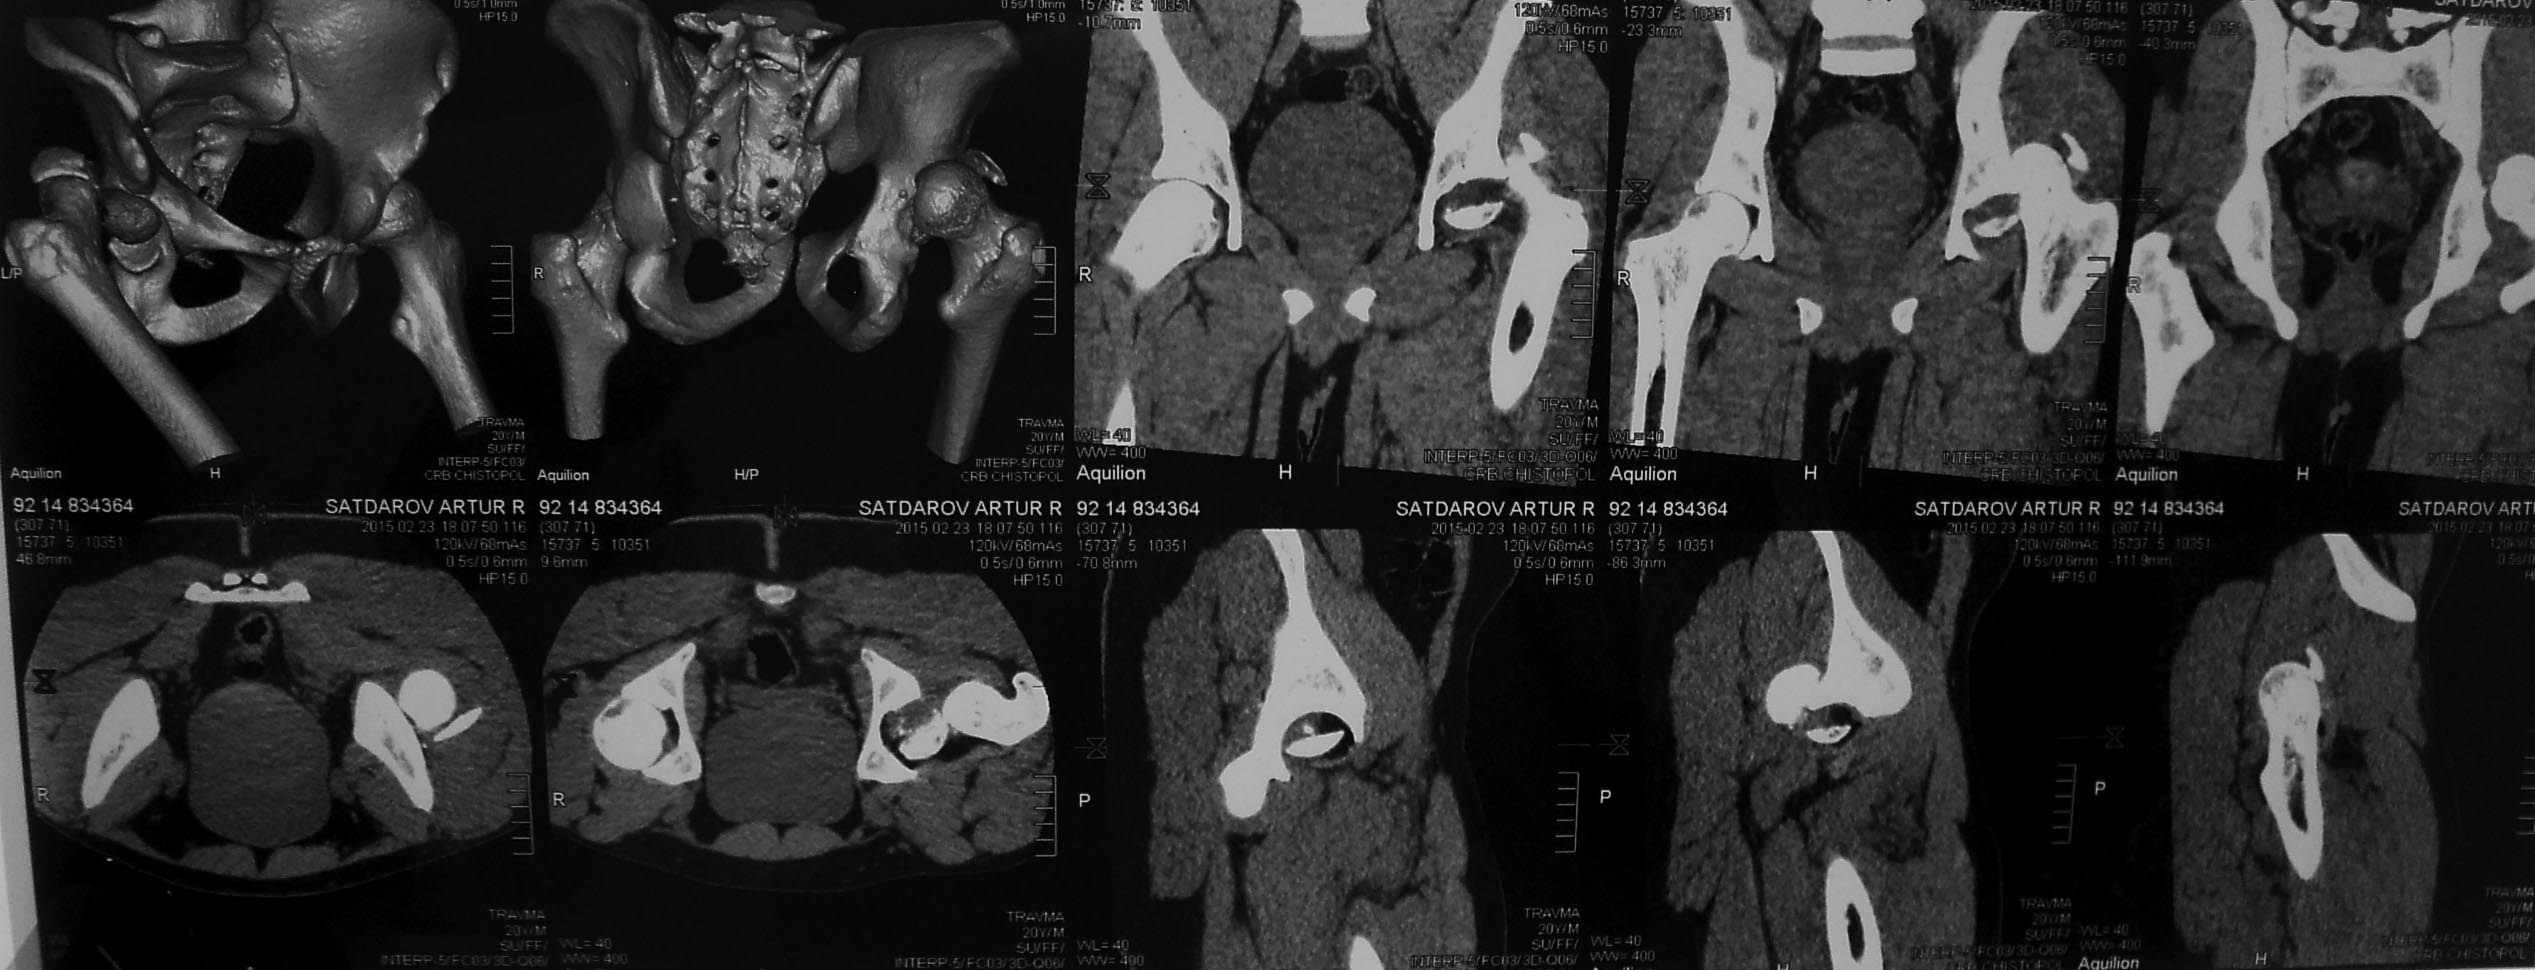

Случай практически идентичный описанный в январе 2015 на ортофоруме Никитой Николаевичем Заднепровским. Молодой человек 20 лет ДТП 23.02.2015, Диагноз: Сочетанная травма. Закрытый переломо-вывих головки и перелом заднего края вертлужной впадины (Pipkin4) правой бедренной кости. Открытый подтаранный вывих правой стопы. При поступлении в ЦРБ вправление вывиха головки бедра и подтаранного вывиха стопы.

Далее перевод к нам в Травмоцентр и 03.03.2015. через 8 дней операция, выполнен остеосинтез головки 3-мя самокомпрессирующими винтами Autofix под разными углами с погружением в субхондральный слой. Доступ Kocher-Langenbeck с флип-остеотомией большого вертела и задним хирургическим вывихом головки бедра. В полости сустава два свободно-лежачих фрагмента хряща головки, которые были удалены. На снимках виден дефект хряща головки после репозиции. Небольшой фрагмент заднего края фиксирован двумя спонгиозными винтами. Далее шов раны с дренированием. На 2 сутки пациент поворачивался на здоровый бок с валиком между ног, на 4 сутки сидел в кровати и на 6 сутки ходил с помощью костылей.